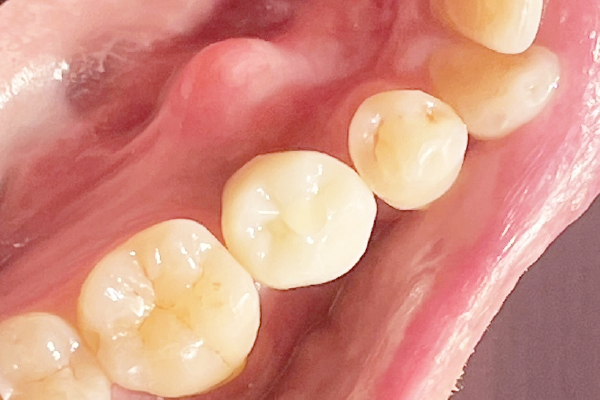

CASE2

インプラントを用いた虫歯治療

| 主訴 | 欠損部分のインプラント埋入 |

|---|---|

| 治療期間 | 3ヶ月(治療回数3回) |

| 治療費 | インプラント1本 330,000円〜385,000円(税込) デンタルローンで月3,000円から始められます |

| 治療の リスク | 治療には神経の治療や抜歯が必要な場合があります。 虫歯や歯周病を防ぐ為に、定期検診にご来院いただきます。 |